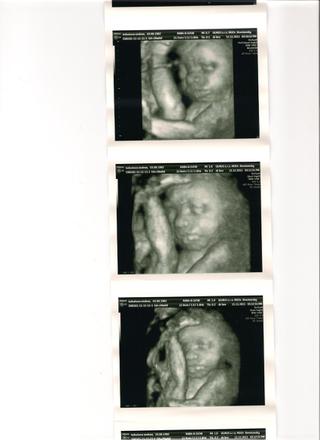

3D sa podariloooooooo.. ratala som s tym, ze to bude kvoli mojej tukovej vstve na brusku horsie.. ale malu celkom pekne vidiet.. hej dobre citate malu 😉 budeme mat DIEVCATKOOOO 😀 straaasne sa tesim... boli somnou svokrovci.. oni jedini mali volno .. hned po ultrazvuku sme utekali kupit nieco ruzove 😝 vybrala som si supravicku do postielky s kraasnymi ruzovymi zirafkami 😝

no a tu je nasa mala princezna 🙂 v 28tt ma 31cm a 1185g.. a je aktobatka.. to pred sebou ma nozku 😅